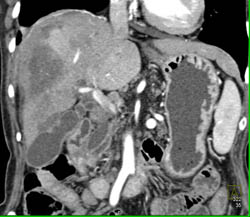

Diagnosis

Liver Infarcts